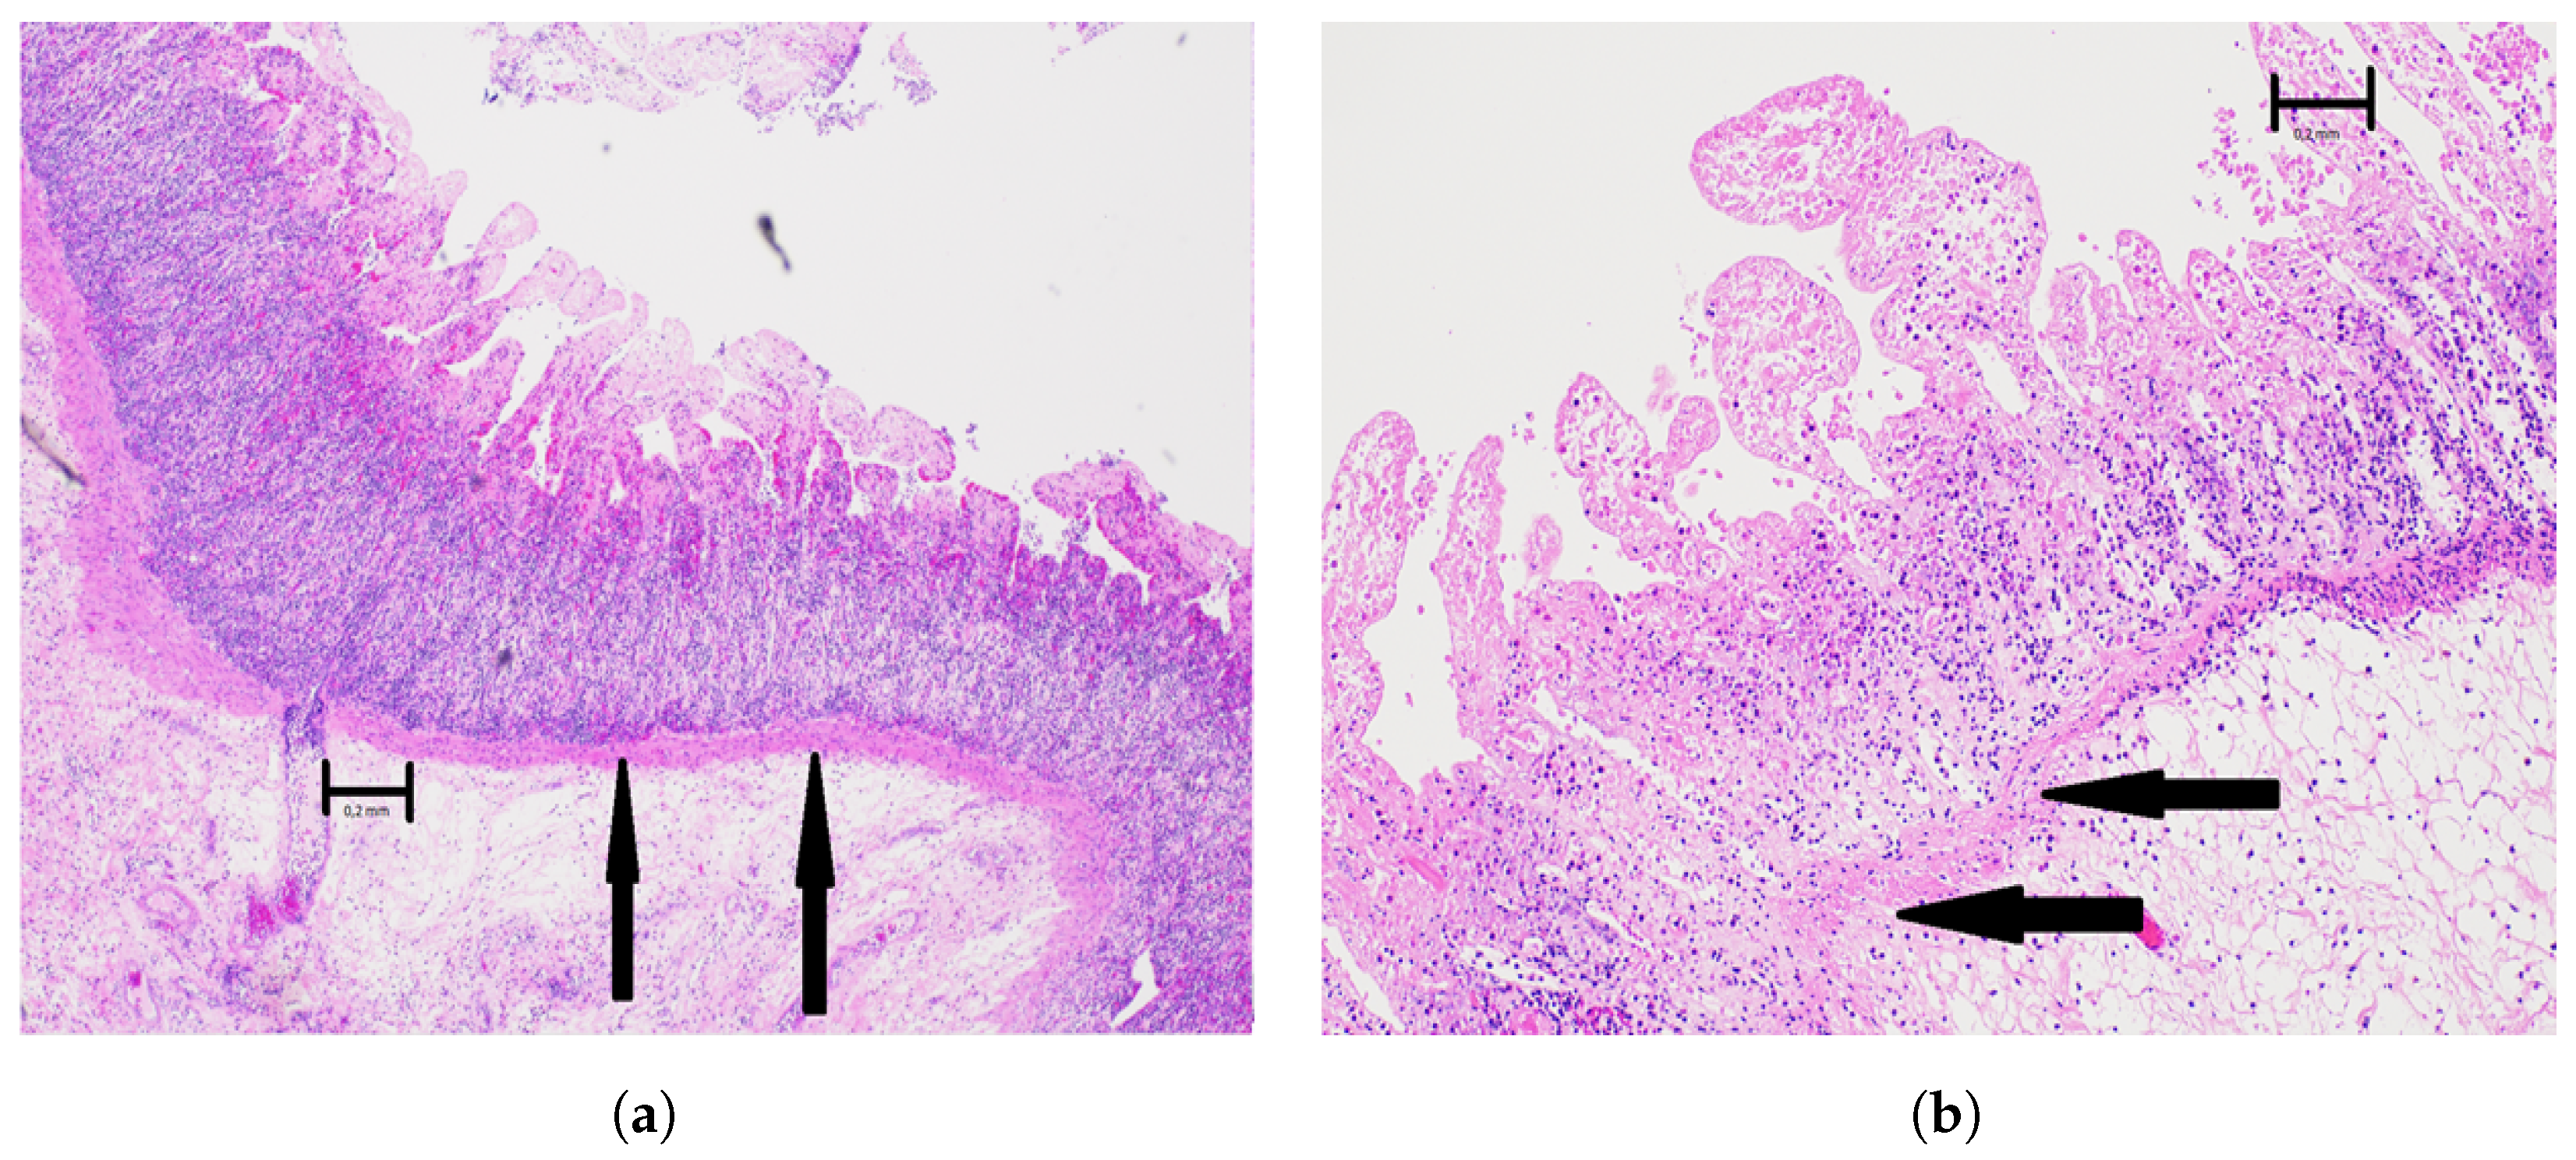

2.4. Histopathological Examination

- Grade 0: No pathological changes;

- Grade 1: Focal loss of surface epithelium in the mucosa;

- Grade 2: Mucosal infarction, with extensive loss of surface epithelium and areas with substance loss in the mucosal lamina propria. Sparing of basal parts of glands, and of the lamina muscularis mucoae;

- Grade 3: Complete mucosal necrosis, variable necrosis of the submucosa, but intact muscularis mucosae;

- Grade 4: Complete necrosis of both the mucosa and the submucosa, and loss of the muscularis mucosae;

- Grade 5: In addition to the changes of grade 4 there are also circulatory disturbances of the inner part of the external muscular layer (lamina muscularis externa);

- Grade 6: Complete necrosis of all layers of the intestinal wall.

Histopathology